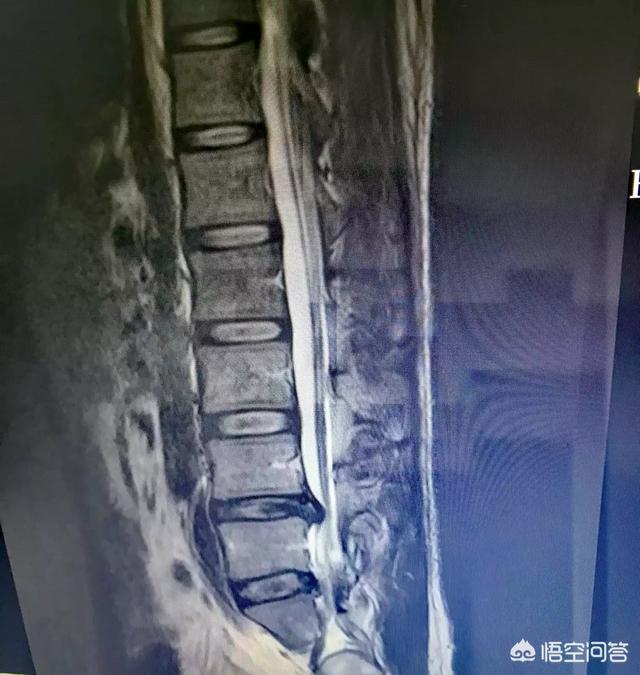

腰椎间盘膨出造成腿痛很易通过触诊来判断,腰部下方多数会有一个明显的压痛点,按压就会出现和症状一致的腿痛,咳嗽打喷嚏也会疼痛,l4-5椎间盘膨出是腿外侧痛,l5-s1椎间盘膨出是腿后侧痛,这都是很典型的确诊表现!